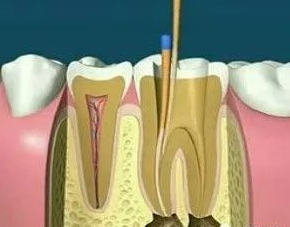

01、什么是根管調(diào)節(jié)?根管調(diào)節(jié),也稱(chēng)為牙髓調(diào)節(jié),是調(diào)節(jié)牙髓疾病和根尖周疾病的有方法。通過(guò)去除根管中的炎性牙髓和壞死物質(zhì)并進(jìn)行適當(dāng)?shù)南?,填充根管以消除根管?nèi)容物對(duì)根尖周?chē)M織的不利刺激,防止根尖周病變的發(fā)生或促進(jìn)根尖周愈合病變。此操作可保護(hù)牙齒,因此可與拔牙互補(bǔ)。根管調(diào)節(jié)很麻煩,通常需要2-4次就診才能完成,并且患者會(huì)遭受更多的痛苦。

2、揭開(kāi)髓腔:去凈腐質(zhì)和原有充填物、揭凈髓頂,看到整個(gè)髓底解剖結(jié)構(gòu)以便后續(xù)調(diào)節(jié)順利進(jìn)行。

5、根管沖洗、消毒:根管沖洗的目的是清除微生物、沖掉殘?jiān)瑵?rùn)滑根管器械和溶解有機(jī)殘?jiān)?。然后,再進(jìn)行根管消毒,使根管內(nèi)達(dá)到無(wú)菌狀態(tài)。

6、根管充填:封閉整個(gè)根管系統(tǒng)、堵塞主根管和側(cè)副根管出口、防止微生物和液體的滲漏。無(wú)論是側(cè)方加壓法還是垂直加壓法,應(yīng)做到根管充填致密,根管充填后X線(xiàn)片上無(wú)根管腔隙,也不能超出根尖孔。